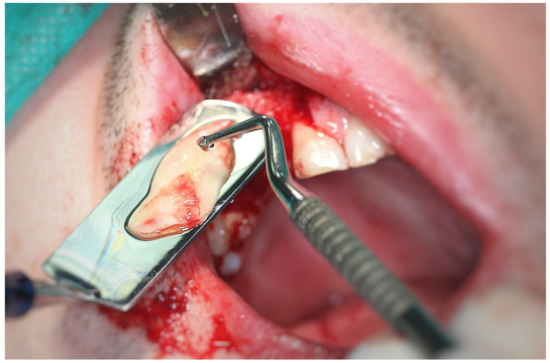

3.2. Surgery